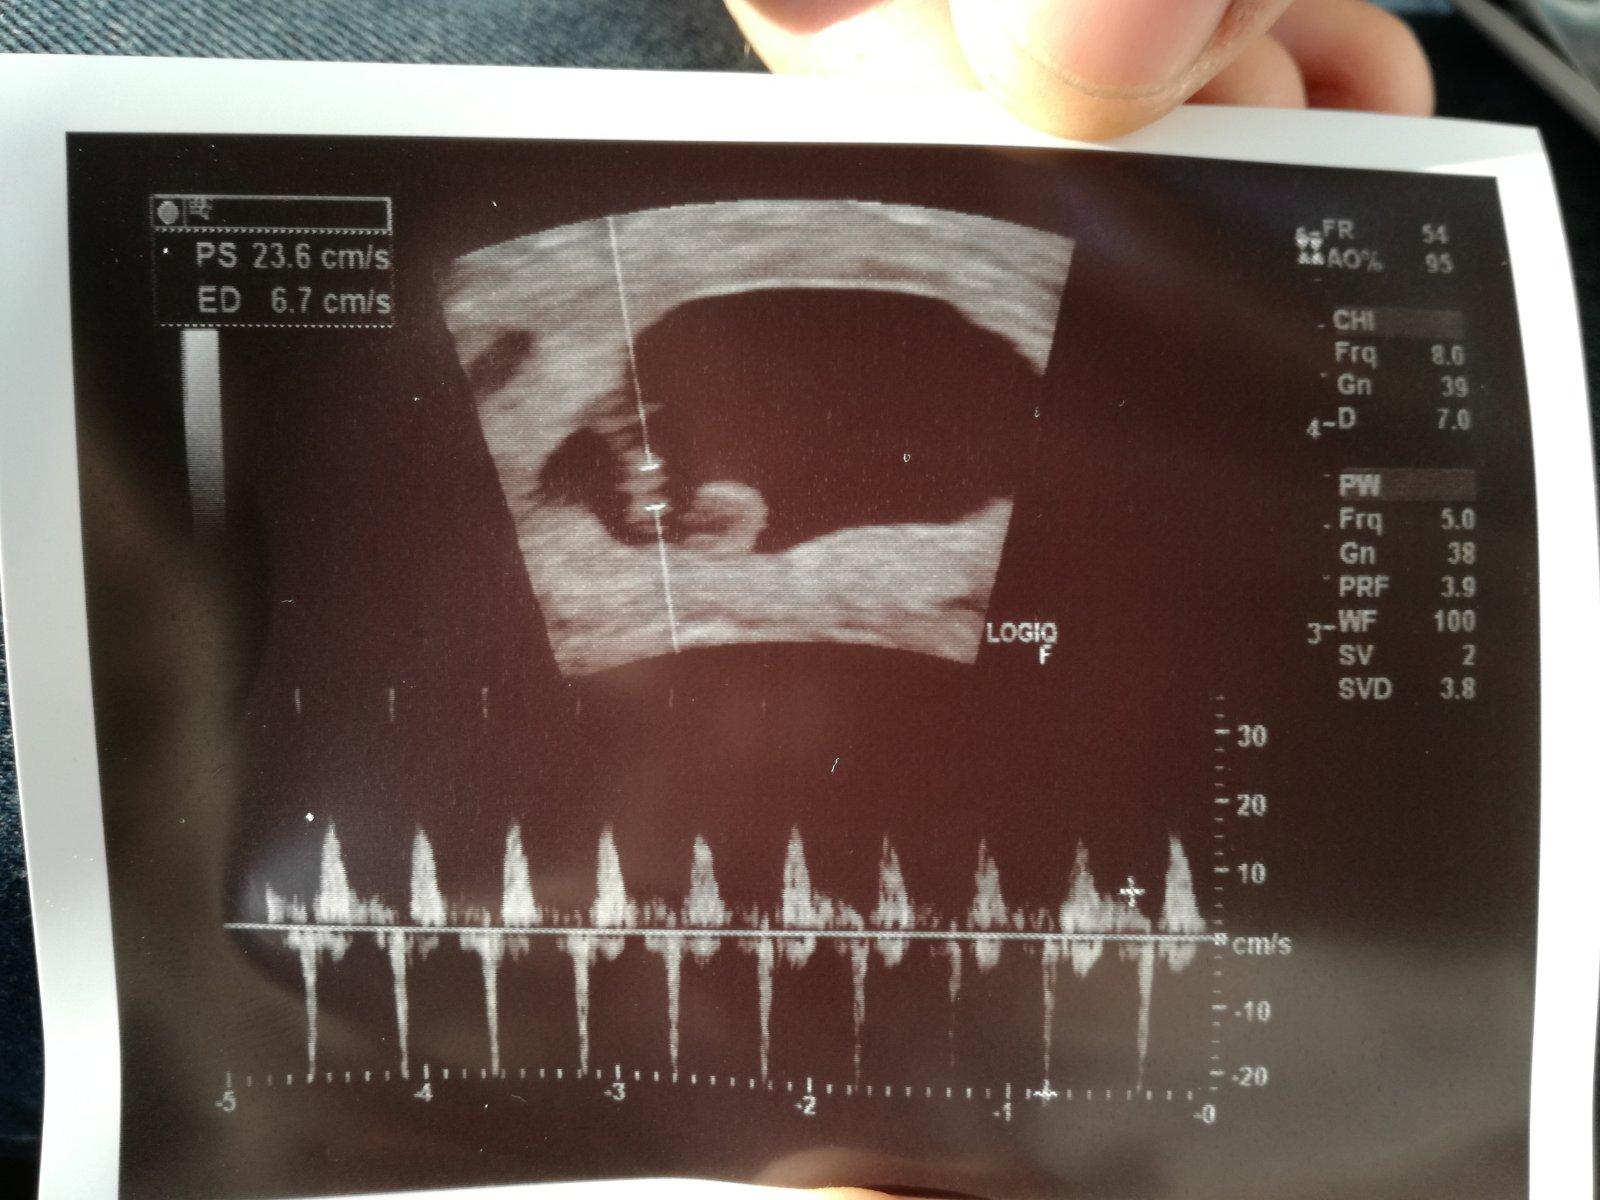

@julinka2787 super 👏🏼👏🏼 A koľko má mm cervicek? @lyzinka o týžden nam ty pridas takúto fotecku 😘

@bobulkapetka 6mm mu nameral Bornayko 😉

@lyzinka dakujem krasne. Si na rade s takymto obrazkom 😊